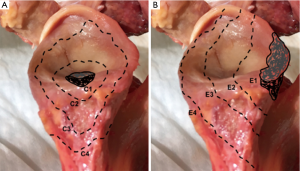

Gupta et al. (44) also presented a classification system to guide intra-operative decision-making for the management of glenoid bone defects (Figure 4). Defects are classified as centric (C), or eccentric (E), and then subclassified according to size (1 to 4) and location (anterior, posterior, inferior or superior). They reported 83% of eccentric (E), 63% of moderate to severe (grades 3 and 4), and 51% of anterior defects in a cohort of 54 revision RSAs (44).